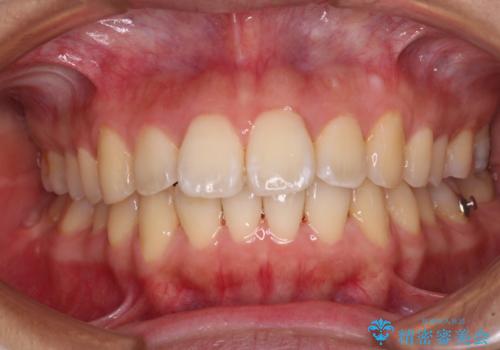

前に出ている前歯を引っ込めたい インビザライン矯正

- 前方に傾斜した上下の前歯を気にして来院された患者様です。

唇の閉じにくさや横顔のシルエットが気になるような突出感ではなかったため、インビザラインを用いて、歯列の遠心移動とIPR(歯と歯の間を削る)により前歯の傾斜を改善していくこととしました。

スムーズに終了すると思われましたが、インビザライン矯正独特の奥歯が咬み合わない状態が続き、更には遠方へ転居されたこともあり、治療期間は長引いてしまいました。